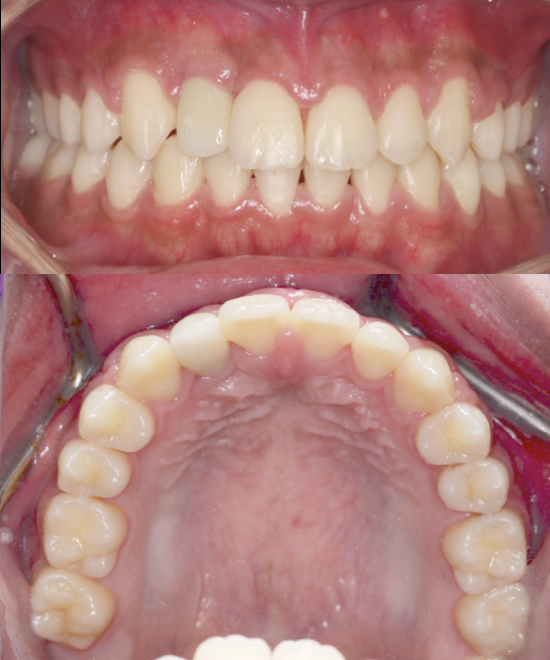

Before

After

BRACES- SEVERE CROWDING

The patient presented with severe upper anterior crowding, rotated teeth, and a constricted arch affecting bite balance and smile aesthetics. The Moral Dental Clinic orthodontic team provided comprehensive  BRACES treatment to align the teeth, correct rotations, and expand the arch for proper occlusion. As a result, the patient achieved a well-aligned upper arch, improved bite, and a cleaner, more harmonious smile.